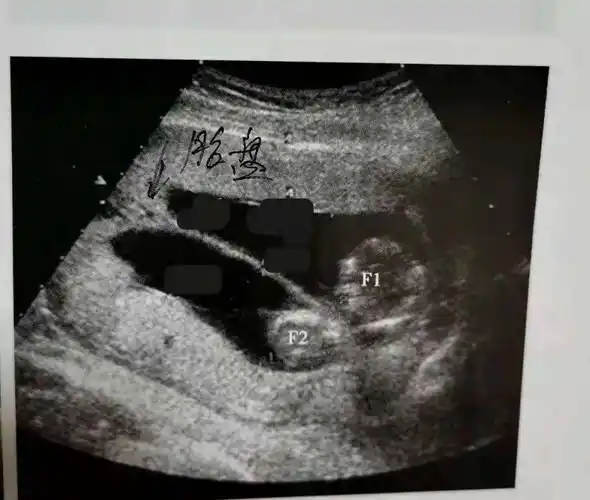

【病例分享】如此典型的轮状胎盘,看过一次就不会忘记_超声